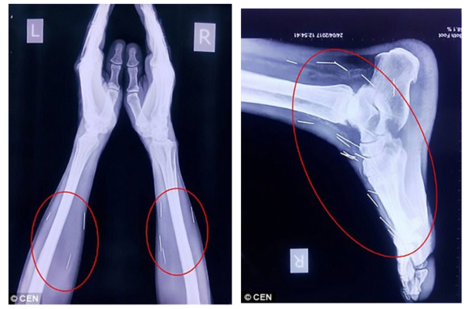

Vietbf.com - Sau khi đau chân đi khám đưa người đàn ông vào bệnh viện để phẫu thuật ngón chân cái, thì bác sĩ phát hiện trong chân ông có nhiều cây kim, khi tiếp tục kiểm tra, các bác sĩ phát hiện có tới 75 cây kim trong cơ thể, có 40 cây nằm trong cổ họng, 25 cây ở chân và 2 cây ở cánh tay, người thân của ông ta cảm thấy vô cùng sợ hãi.

Thế nhưng, trong quá trình chụp X-quang để kiểm tra tổng thể, các bác sĩ đã vô cùng sửng sốt khi phát hiện có đến 75 chiếc kim đâm trên khắp người bệnh nhân, từ cổ, vai cho đến chân.

Chân và tay bệnh nhân cũng có hàng chục cây kim khác. Ảnh: DAILY MAIL

Cho đến nay, vẫn chưa một bệnh viện nào trong số những nơi ông Meena đến thăm khám đồng ý rút kim ra khỏi cơ thể cho ông ta. Trong số 75 chiếc kim nói trên, có 40 chiếc đâm quanh khu vực họng, 25 chiếc đâm ở chân, còn lại là ở những chỗ khác.